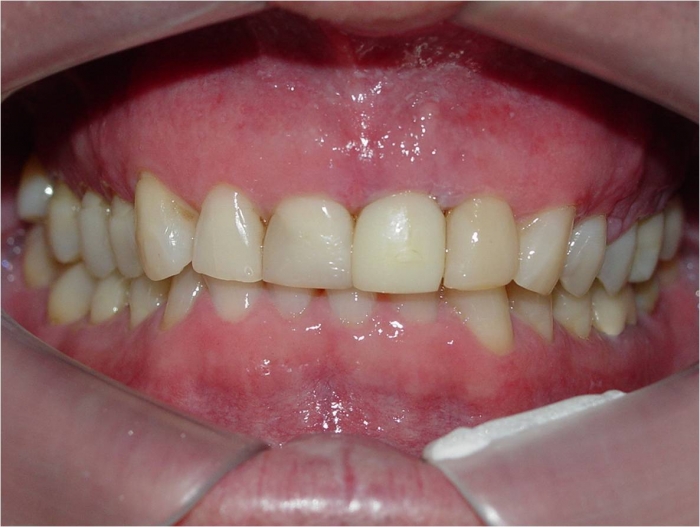

Sorriso inicial

Mordida inicial